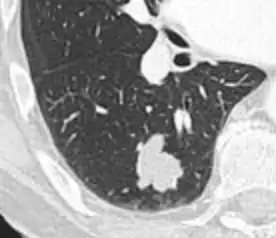

- A lung nodule abutting a pulmonary cyst is a rare finding, yet indicating cancer.[9]

- Bubble-like lucencies in the nodule indicate cancer:[9]

- Vascular convergence is where vessels converge to a nodule without adjoining or contacting the edge of the nodule, and is mainly seen in peripheral subsolid lung cancers.[9] It reflects angiogenesis.[9]

Air bronchograms is defined as a pattern of air-filled bronchi on a background of airless lung, and may be seen in both benign and malignant nodules, but certain patterns thereof may help in risk stratification.[9]